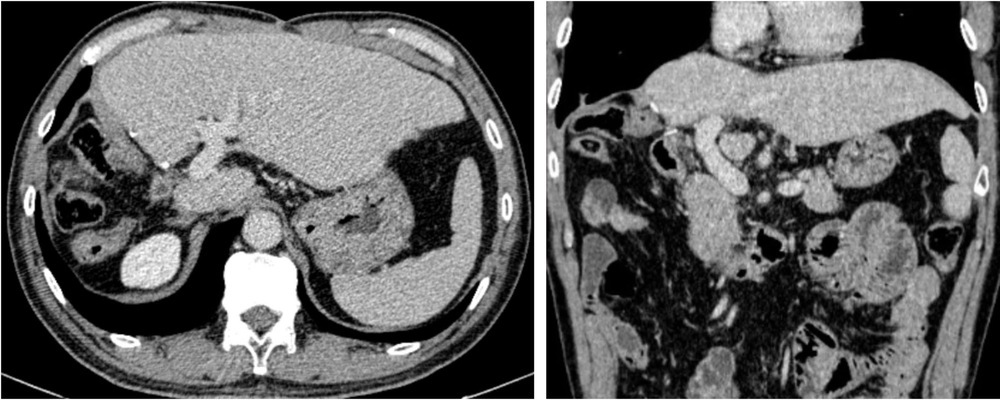

Hình ảnh chụp cắt lớp vi tính sau phẫu thuật 4 năm. Bệnh nhân gan trái tốt, tĩnh mạch cửa thông thoáng, không có tái phát tại gan và di căn xa. Ảnh: BV

Chiến lược này nhằm mục tiêu đạt hiệu quả cao nhất và bảo đảm an toàn cho người bệnh. Sau 4 năm tái khám, các kết quả kiểm tra xác định bệnh nhân không có khối u tái phát. Chức năng phần gan còn lại của ông Đ. đang hoạt động rất tốt và các bác sĩ cũng không tìm thấy bất kỳ dấu hiệu di căn xa nào trên cơ thể bệnh nhân.